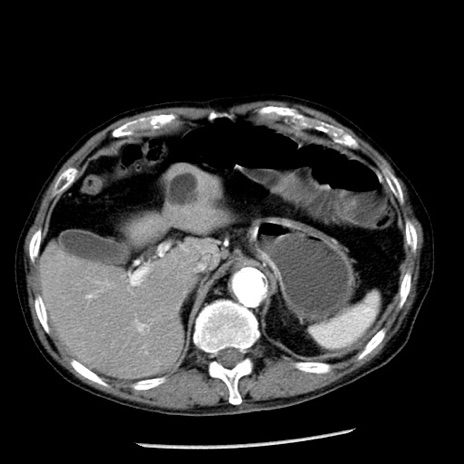

症例26(横断像)

冠状断像

【症例】80歳代男性

【主訴】嘔吐

【現病歴】昨晩2回嘔吐あり、今朝になっても嘔吐あり。来院。

【既往歴】胃潰瘍

【身体所見】意識清明、BT 37.6℃、BP 166/95mmHg、HR 100bpm、SpO2 97%、腹部:平坦・軟、腸蠕動音聴取良好、圧痛なし。

【データ】WBC 21900、CRP 1.46